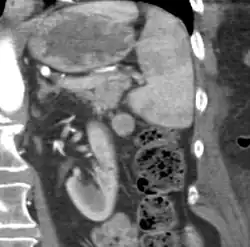

| CT scan of an accessory spleen (circular object in center of image) between the spleen and left kidney. | |

An accessory spleen is a small nodule of splenic tissue found apart from the main body of the spleen. Accessory spleens are found in approximately 10 percent of the population[1] and are typically around 1 centimeter in diameter. They may resemble a lymph node or a small spleen. They form either by the result of developmental anomalies or trauma.[2] They are medically significant in that they may result in interpretation errors in diagnostic imaging[2] or continued symptoms after therapeutic splenectomy.[1] Polysplenia is the presence of multiple accessory spleens rather than one normal spleen.

If splenectomy is performed for conditions in which blood cells are sequestered in the spleen, failure to remove accessory spleens may result in the failure of the condition to resolve.[1] During medical imaging, accessory spleens may be confused for enlarged lymph nodes or neoplastic growth in the tail of the pancreas,[5] gastrointestinal tract, adrenal glands or gonads.[2]